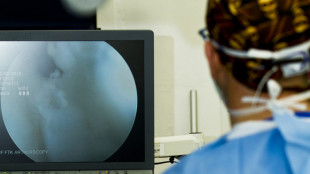

Chirurgia senza sangue, al Pascale la svolta robotica sul fegato

Prima resezione epatica con Hemo Diss, 'più sicurezza, rapidità e perdite ematiche minime'